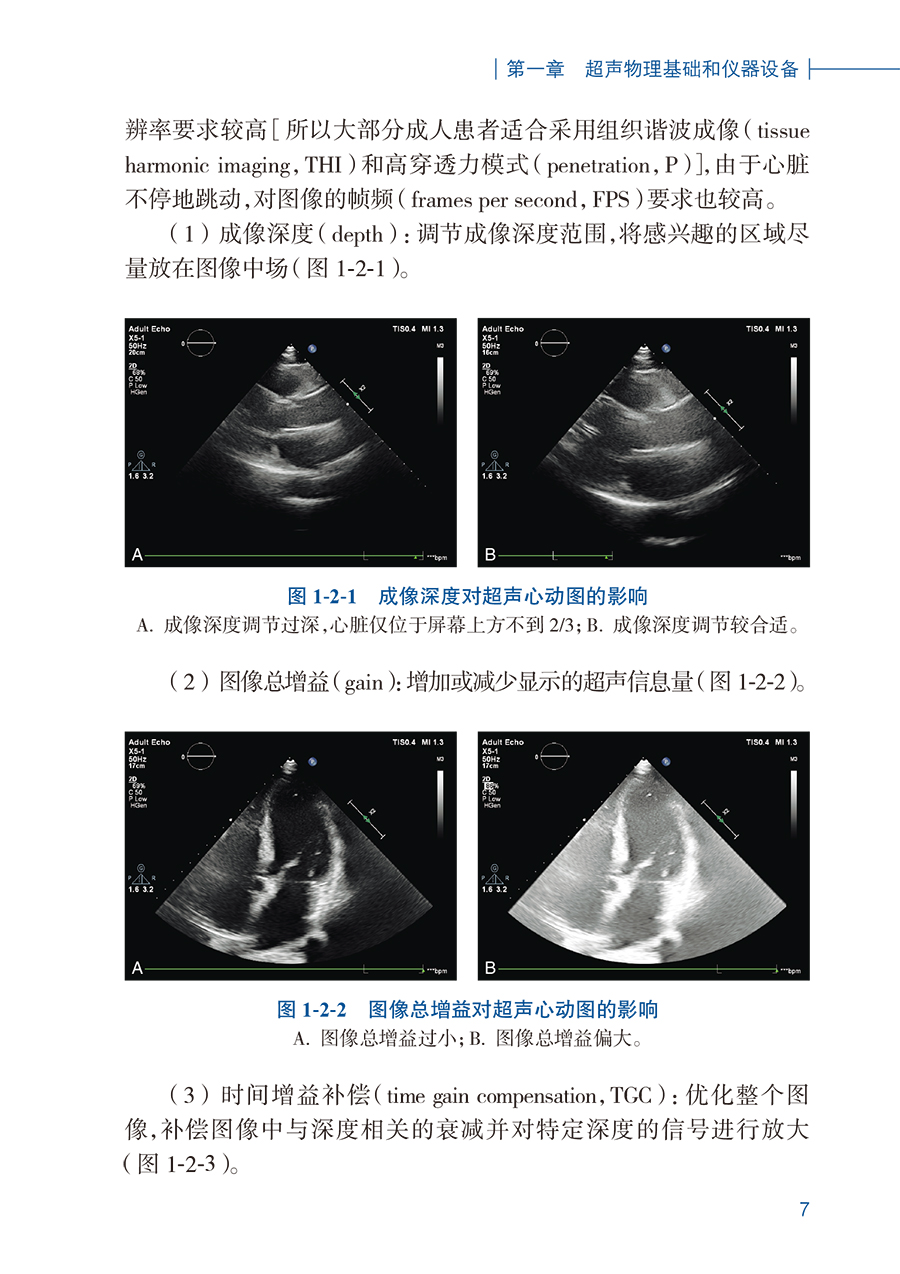

【1】简要阐述心脏超声物理基础和基本技术方法,新技术发展。【2】各种先天性心脏病病理和血流动力学、超声表现、图像及诊断要点。【3】各种常见获得性(后天性)心脏病,包括冠心病、心肌病、瓣膜病、心包疾病、心脏肿瘤等的超声诊断表现和价值。【4】急重症心血管疾病的超声应用愈加广泛和重要,本书单列一章进行叙述要点。【5】集合了外周血管的常见病超声检查。【6】辅以阜外医院丰富的各种心血管疾病治疗的超声诊断、疗效评价病例资料。【7】图文并茂,超声心动资料将以视频形式呈现给读者。